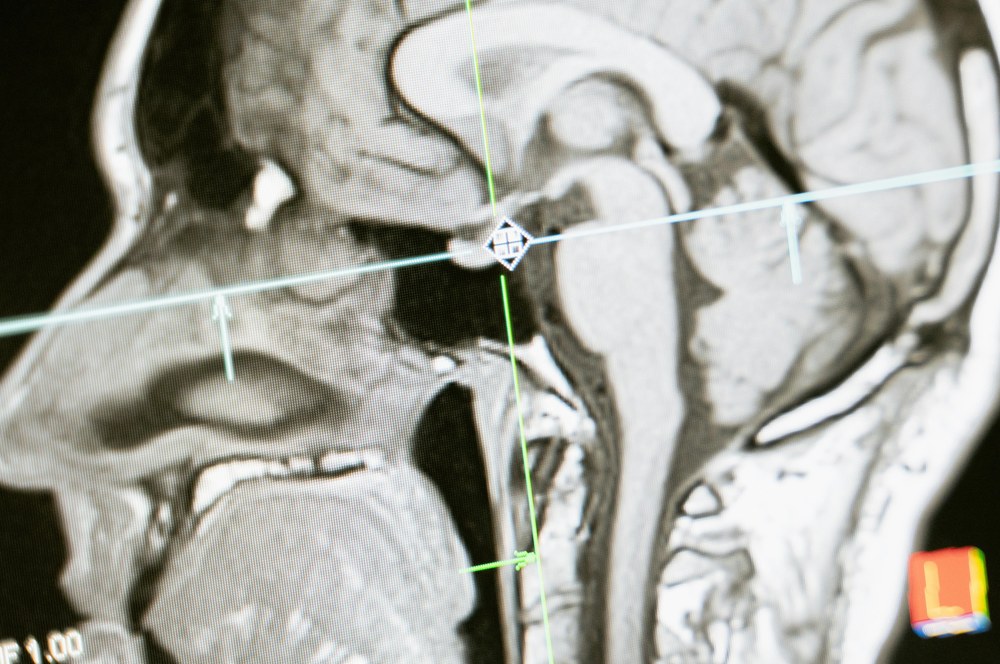

Уявіть, що лікар намагається визначити точне розташування нерва перед встановленням імпланта, але традиційні методи виявляються безсилі. Або ж ви відчуваєте стійкий біль, але рентген показує лише порожнечу. В таких випадках комп’ютерна томографія (КТ) стає незамінною, надаючи повну картину того, що коїться всередині.

Ця технологія дозволяє отримати об’ємне зображення щелепи, зубів, кісткової тканини й гайморових пазух. Лікар бачить не лише поверхню, але й глибину, нахил, щільність. Завдяки цьому він діє точно, а не працює «наосліп». У клініці «Галлант» у Корсуні, де кожен хвилина й здоров’я пацієнтів мають значення, КТ не є розкішшю, а частиною основного підходу до лікування.